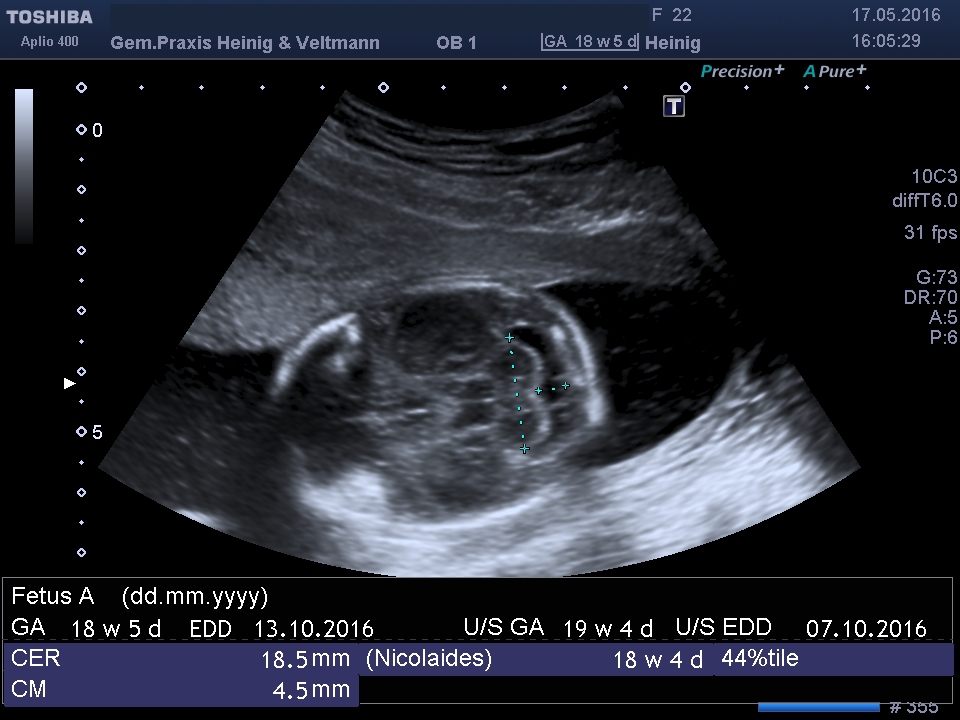

Bei der zweiten Ultraschall-Untersuchung zwischen der 19. und 22. Schwangerschaftswoche können Schwangere zwischen zwei Möglichkeiten wählen: zwischen der Basis-Ultraschalluntersuchung und der erweiterten Basis-Ultraschalluntersuchung.

Bei der Basis-Ultraschalluntersuchung wird die altersgerechte Entwicklung des Kindes überprüft. Die Größe von Kopf und Bauch sowie die Länge des Oberschenkelknochens werden gemessen und die Fruchtwassermenge bestimmt. Außerdem wird die Lage des Mutterkuchens in der Gebärmutter kontrolliert. Bei einem zu tiefen Sitz können bei der weiteren Betreuung und für die Geburt besondere Vorkehrungen nötig werden. Ergeben sich Auffälligkeiten, können sie durch weitere Untersuchungen abgeklärt werden.

Bei der erweiterten Basis-Ultraschalluntersuchung wird zusätzlich noch überprüft, ob sich Kopf, Hirnkammern und Kleinhirn des Kindes normal entwickeln. Das Größenverhältnis von Brustkorb und Herz wird gemessen und der Herzschlag kontrolliert. Auch wird festgestellt, ob Bauchwand, Hals und Rücken geschlossen und Magen und Harnblase sichtbar sind. Der erweiterte Basis-Ultraschall ist eine Leistung der gesetzlichen Krankenkassen. Er wird seit Januar 2014 von allen Krankenkassen bezahlt. Zeigen sich bei einer Ultraschall-Untersuchung Auffälligkeiten, kann die Schwangere weitere Untersuchungen in Anspruch nehmen, beispielsweise eine Chorionzottenbiopsie (Gewebeprobe aus dem Mutterkuchen) oder eine Fruchtwasseruntersuchung.